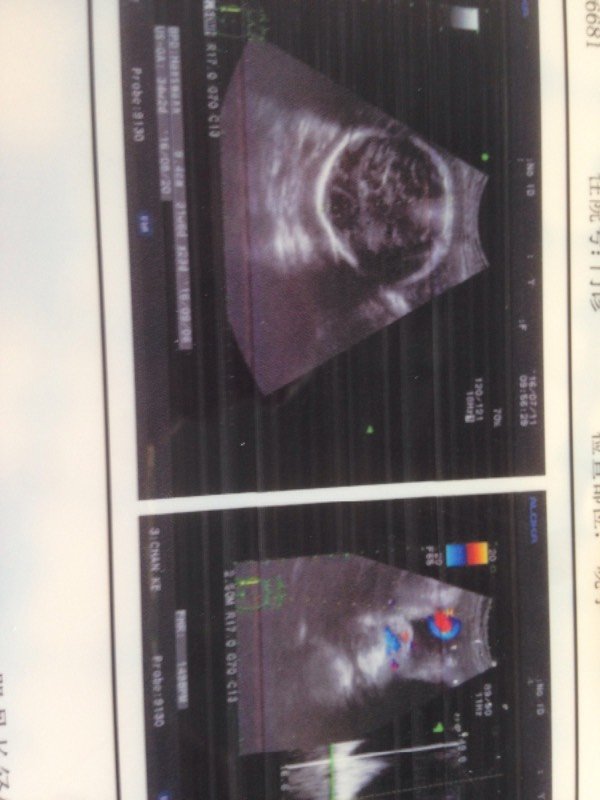

看不懂bc图,有没有宝妈帮忙看看图中显示的是什么,能看出男孩女孩么 看不懂bc图,有没有宝妈帮忙看看图中显示的是什么,能看出男孩女孩么? 点击展开 刘淋龙 2016-07-28 10:10 推荐回答 身满厉边朋友B超竞搂唤如果是女孩很容易翻盘的,貌似只有生下来最准了~~~~可以过几个月再去看看,如果宝宝没有射毫背过去的话 匿名用户 2016-07-28 10:11 宝宝知道提示您:回答为网友贡献,仅供参考。 相关问题 帮忙看看b超图,是男孩女孩啦 怀双胞胎16周+6了,宝妈帮忙看看男孩女孩啊!